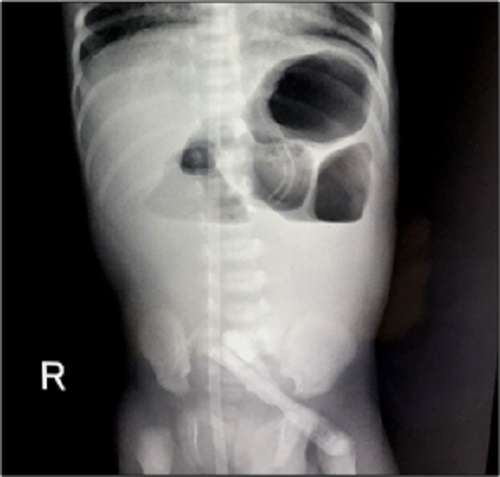

X-ray abdomen showed few air-fluid levels which were suggestive of proximal jejunal atresia (Fig. 1). USG abdomen, in addition to distended small bowel loops, surprisingly revealed a distended ascending colon which was filled with thick fluid suggestive of obstruction in the distal large bowel.

Figure 1

X-Ray Abdomen showing few air-fluid levels suggestive of jejunal atresia.